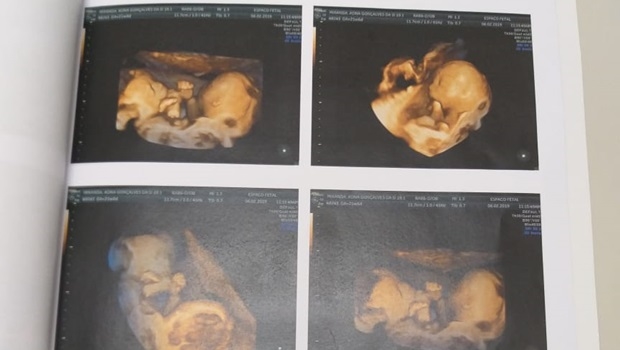

O médico cirurgião pediátrico Zacharias Calil foi eleito deputado federal pelo Democratas, o que não o impediu de dar continuidade ao seu trabalho na área de saúde. Na tarde desta sexta-feira, 8, ele atendeu, no Hospital Materno Infantil, um caso raro de gêmeos conjugados (siameses) – a mãe está de 26 semanas.

Segundo o médico, os dois irmãos (ambos do século masculino) estão ligados pelo tórax, abdômen e bacia. Destaca-se que este tipo de ocorrência corresponde a apenas 6% no histórico de siameses. Os pais, que vieram do Espírito Santo, preferiram permanecer anônimos. Eles têm uma filha de 15 anos.

Este será o 39º caso de Zacharias. Ele explica que os meninos compartilham o fígado, provavelmente o intestino e órgão genital, e podem apresentar alguma complicação cardíaca. “Eles possuem quatro pernas. Me lembra o caso do Arthur e do Heitor, que tinham três”, e foram separados fevereiro de 2015, no Materno Infantil.